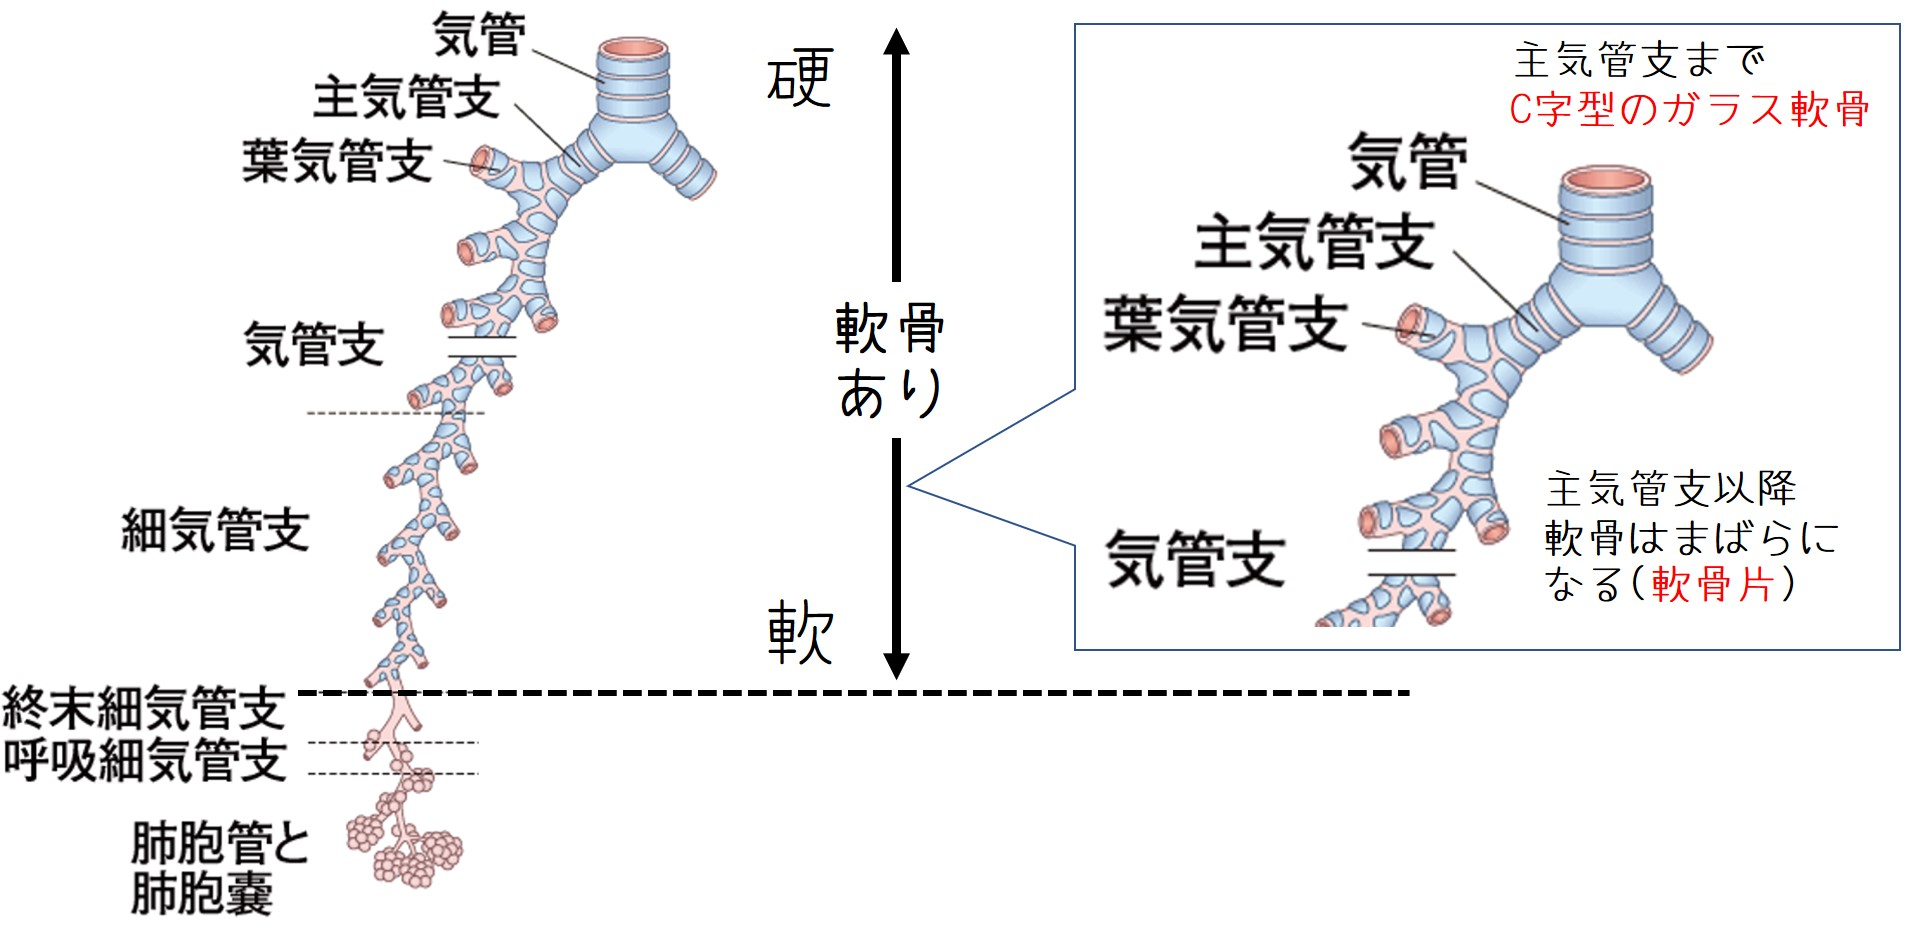

選ぶなら 気道・肺の腫瘍 (呼吸器病New Approach 9) | 飛田 渉 |本 | 通販 医学一般